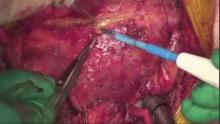

Several technical tips and pitfalls are critical when performing unroofing. It is advisable to perform the procedure on the arrested heart. It is important to properly identify the coronary artery via cardioplegic administration, use of intraoperative fluorescent angiography with indocyanine green, and moving from the non-intramyocardial to the intramyocardial segments. It is not advised to directly incise the myocardium on top of the intramyocardial coronary artery as it may result in injury of the coronary artery or ventricular free wall perforation. A combination of Potts scissors and electrocautery are useful for dissection.

This video presents a case of a ten-year-old boy with Noonan syndrome who underwent left ventricular septal myectomy at a different institution and presented with chest pain that occurred with exertion. The chest pain led to repeated hospitalization, and an exercise test was terminated because of the chest pain. Coronary angiography showed significant and long deep myocardial bridge affecting the left anterior descending (LAD) coronary artery.

A repeat sternotomy was performed, and the LAD was completely unroofed. The patient recovered from surgery and has been free from chest pain for the duration of his follow-up.